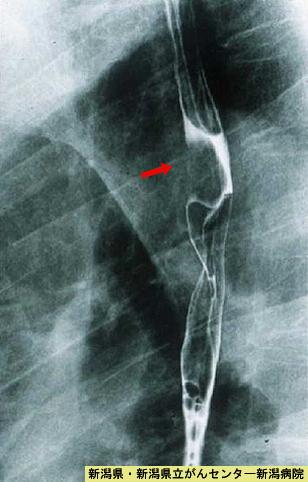

症例提示(所在地,施設名等): 新潟県・ 新潟県立がんセンター (Dr.秋山ら)

疾患(病理主体)の分類良性非上皮性腫瘍/血管腫

部位(臓器別)食道/上

検査方法X-P

病変の最大径(ミリ)15〜19